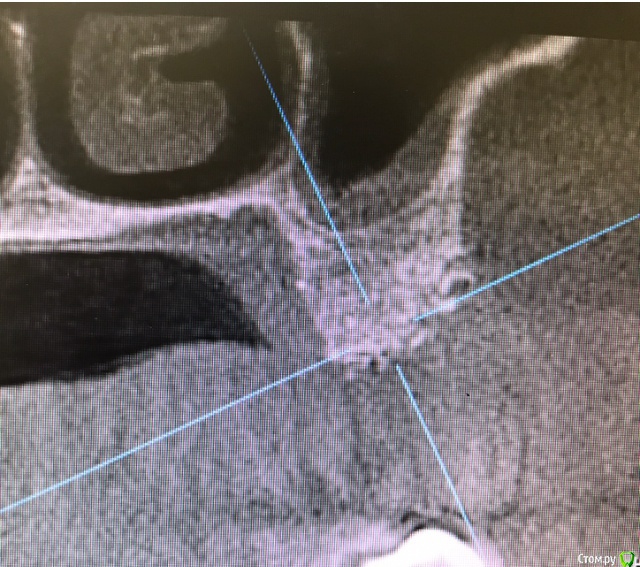

колесников Опубликовано 20 августа, 2019 Автор Поделиться Опубликовано 20 августа, 2019 Очередной случай тоннельной пластики альвеолярного гребня. Был небольшой бонус в виде лунки 26го зуба с дефектом вестибулярной стенки и оас. Лунка консервирована и закрыта «быстрым Ноймайером»,24,25 тоннельный графтинг. Графт тот же,шурос кортикальный без добавок.Контроль и имплантация через 4 мес,через неделю фиксация временной реставрации. Через 2-3 проверим на состоятельность. 4 Ссылка на комментарий